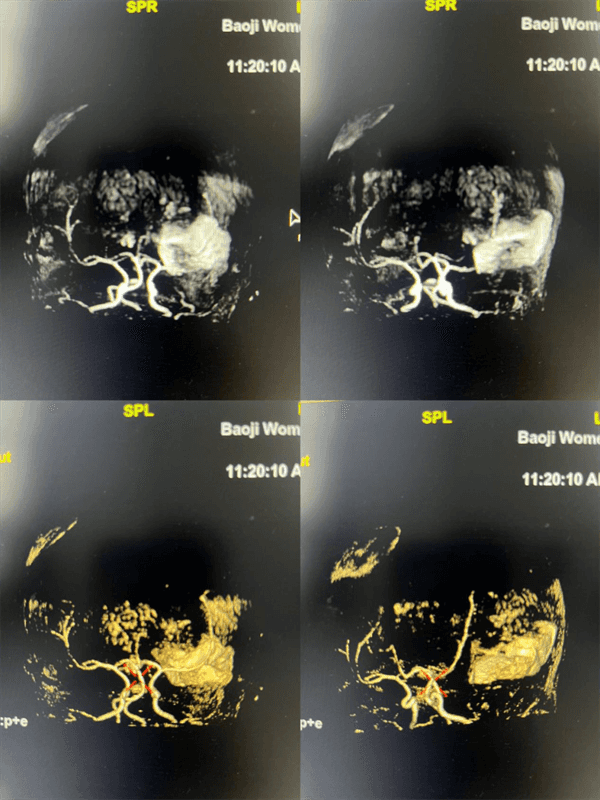

检查结果很快出来了:影像清晰地显示,宝宝左侧部分颞叶、枕叶存在亚急性脑出血,并且血肿已经破入双侧侧脑室。同时,MRA检查还发现了右侧大脑前动脉的发育异常。这份精准的影像报告,就像一张清晰的“大脑地图”,让临床医生对宝宝的病情一目了然,使得治疗更加“有的放矢”。